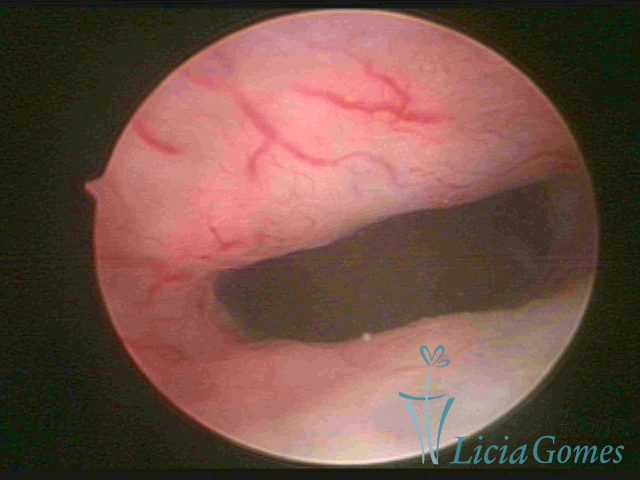

After the resection of the suture in Retraction of a cesarean section scar